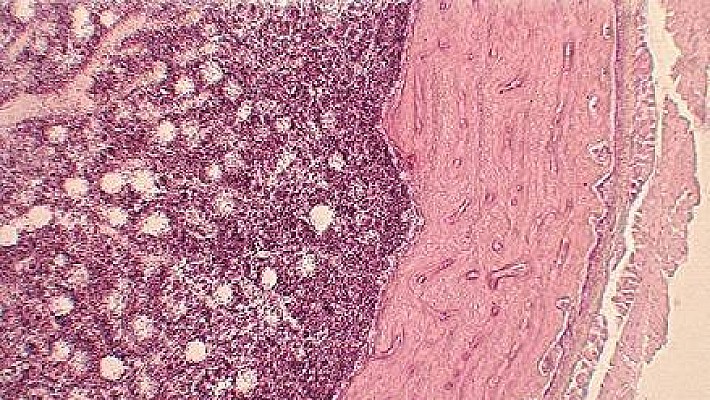

Marrow transplant cures adult sickle cell disease